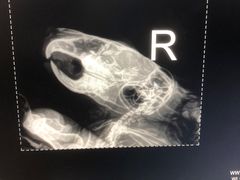

• 瑞派·关忠动物医院·异宠专科·犬猫肿瘤·皮肤专科(望京店)

• -瑞派·关忠动物医院·异宠专科·犬猫肿瘤·皮肤专科(望京店)

染染子 | 22-07-16